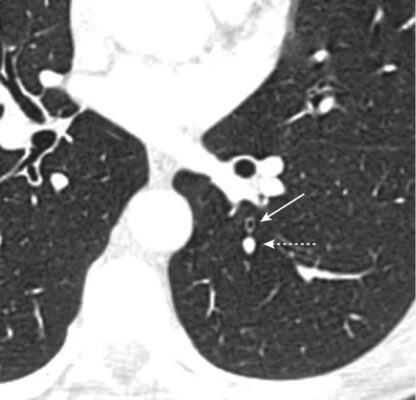

- Các phế quản và tiểu phế quản cũng có thể nhìn thấy được, và theo quy luật, các phế quản thường nhỏ hơn các động mạch phổi đi kèm (Hình 13).

CÁC RÃNH LIÊN THUỲ

- Tùy thuộc vào độ dày của lát cắt, các rãnh sẽ có thể nhìn thấy dưới dạng các đường trắng mỏng hoặc bằng một dải vô mạch dày khoảng 2 cm khi chúng đi chéo qua phổi (Hình 16).

- Rãnh nhỏ đi cùng mặt phẳng ngang như với hình ảnh CT cắt ngang nên thường không thể nhìn thấy, ngoại trừ ở mặt phẳng đứng dọc hoặc mặt phẳng trán. Tuy nhiên, giống như các rãnh lớn, có thể suy luận ra vị trí của rãnh nhỏ bởi một vùng vô mạch giữa các thùy trên và thùy giữa phải (xem Hình 16, A).

- Rãnh lớn phân cách thuỳ trên với thuỳ thấp hơn. Ở bên phải, rãnh bé phân chia thùy giữa. Tương tự của nó ở bên trái là phân thuỳ lưỡi của thùy trên trái (Hình 17).